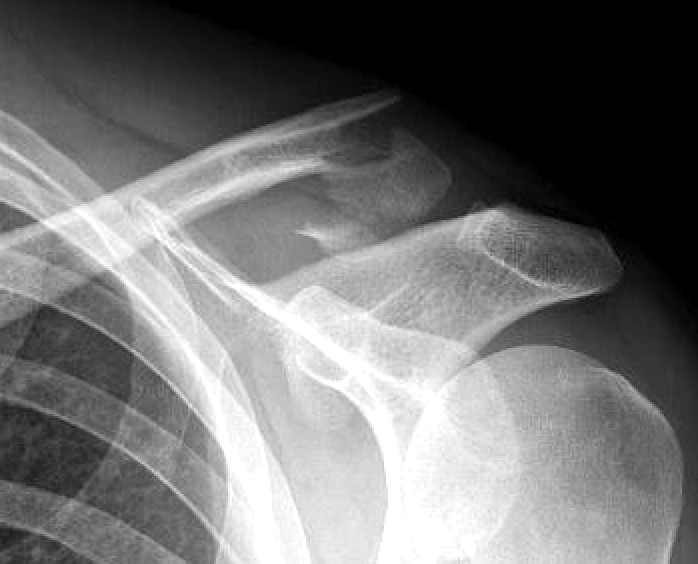

Neer Classification

Fracture lateral to the CC ligaments Non displaced

|

Fracture medial to the CC ligaments CCL ligaments attached to lateral fragment Medial fragment displaced superiorly |

Between conoid and trapezoid Conoid disrupted Trapezoid remains attached to the lateral fragment |

Type I

Type II